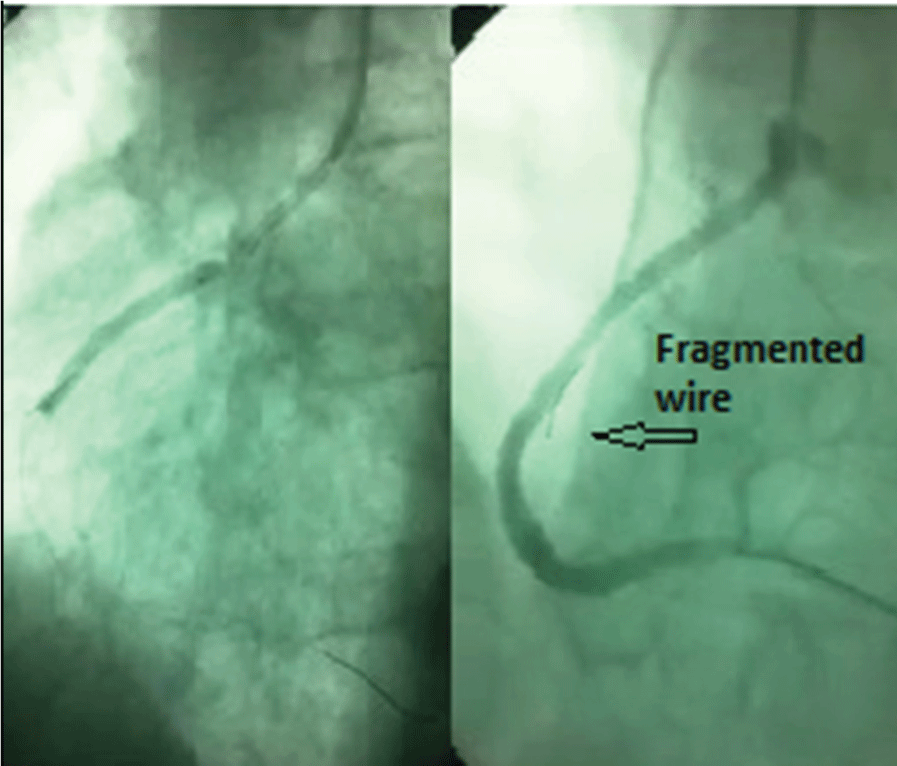

A 56-years old man was admitted to our cardiology outpatient department with Canadian Cardiac Society Class II stable angina pectoris that has been continuing for the last six months. His past medical history revealed hypertension and hyperlipidemia. Myocardial perfusion scintigraphy demonstrated inferior ischemia and diagnostic coronary angiography showed a long CTO of the right coronary artery (RCA) and retrograde distal filling of RCA from septal collateral channels of left anterior descending artery (Figure 1). Afterwards, percutaneous coronary intervention (PCI) to CTO of RCA was planned. We decided to recanalize the occluded vessel by using antegrade approach. RCA was cannulated with a left amplatz 1 guiding catheter and a stiff guidewire with a tip load of 9 grams (Conquest Pro, Asahi, Intecc) was chosen to penetrate the proximal cap with the support of a microcatheter (Corsair, Asahi, Intecc) due to the absence of microchannels. Conquest Pro succeeded to penetrate the proximal cap of the occlusion, however it went subintimally and caused a dissection which was endorsed by over-manipulation of the guidewire. We tried to remove the guidewire but it was trapped and we failed to pull it out. Therefore, we applied a more forceful and aggressive traction to extract it and succeeded in pulling it out however we saw that the guidewire was broken from its tip. Coronary angiography revealed that the tip of Conquest Pro guidewire was still in the subintimal space (Figure 2).

Figure 1: Coronary angiography displaying a long chronic total occlusion of the right coronary artery and retrograde distal filling from septal collateral channels of the left anterior descending artery (black arrow).

Figure 2: Coronary angiographic views demonstrating the coronary dissection and fractured guidewire in subintimal space.